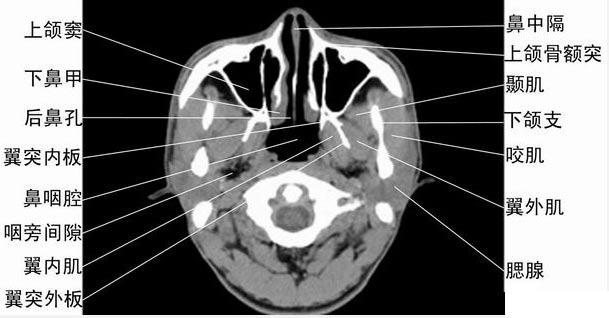

ct轴位鼻腔和鼻窦层面(图)

鼻窦ct怎么看图解解剖

鼻窦ct怎么看图解

鼻窦ct怎么看图解断层

鼻窦ct解剖图

鼻窦ct解剖